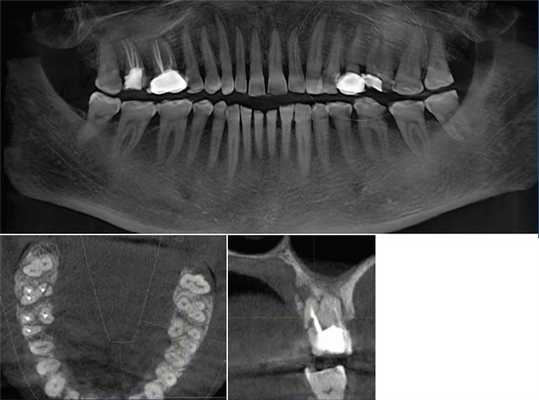

Через год пациентка была направлена на повторную КЛКТ с целью радиомониторинга.

Описание рентгенологического исследования 4.6, 4.7 зубов в динамике. 4.6 зуб депульпирован. Коронковая часть восстановлена пломбой. Краевое прилегание не нарушено. Строение канально-корневой системы: 2 корня, 5 каналов. Все каналы заполнены пломбировочным материалом плотно, на всем протяжении. Пространство периодонтальной связки и периапикальные ткани не изменены. Твердая пластинка альвеолы прослеживается на всем протяжении (рис. 8, 9) .

Рис. 8. КЛКТ, МПР. Оценка качества обтурации каналов мезиального корня 4.6 зуба.

Рис. 9. КЛКТ, МПР. Оценка качества обтурации каналов дистального корня 4.6 зуба.

4.7 зуб депульпирован. Коронковая часть восстановлена пломбой. Краевое прилегание не нарушено. Строение канально-корневой системы: 2 корня, 5 каналов. Все каналы запломбированы гомогенно, полностью. Сохраняется краевая апикальная резорбция дистального корня. Наблюдается практически полная регенерация очага деструкции в проекции верхушек обоих корней. Имеется остаточное расширение апикального периодонта в области дистального апекса (рис. 10, 11) .

Рис. 10. КЛКТ. МПР. Оценка качества обтурации каналов мезиального корня 4.7 зуба и состояния периапикальных тканей.

Рис. 11. КЛКТ. МПР. Оценка качества обтурации каналов дистального корня 4.7 зуба и состояния периапикальных тканей.